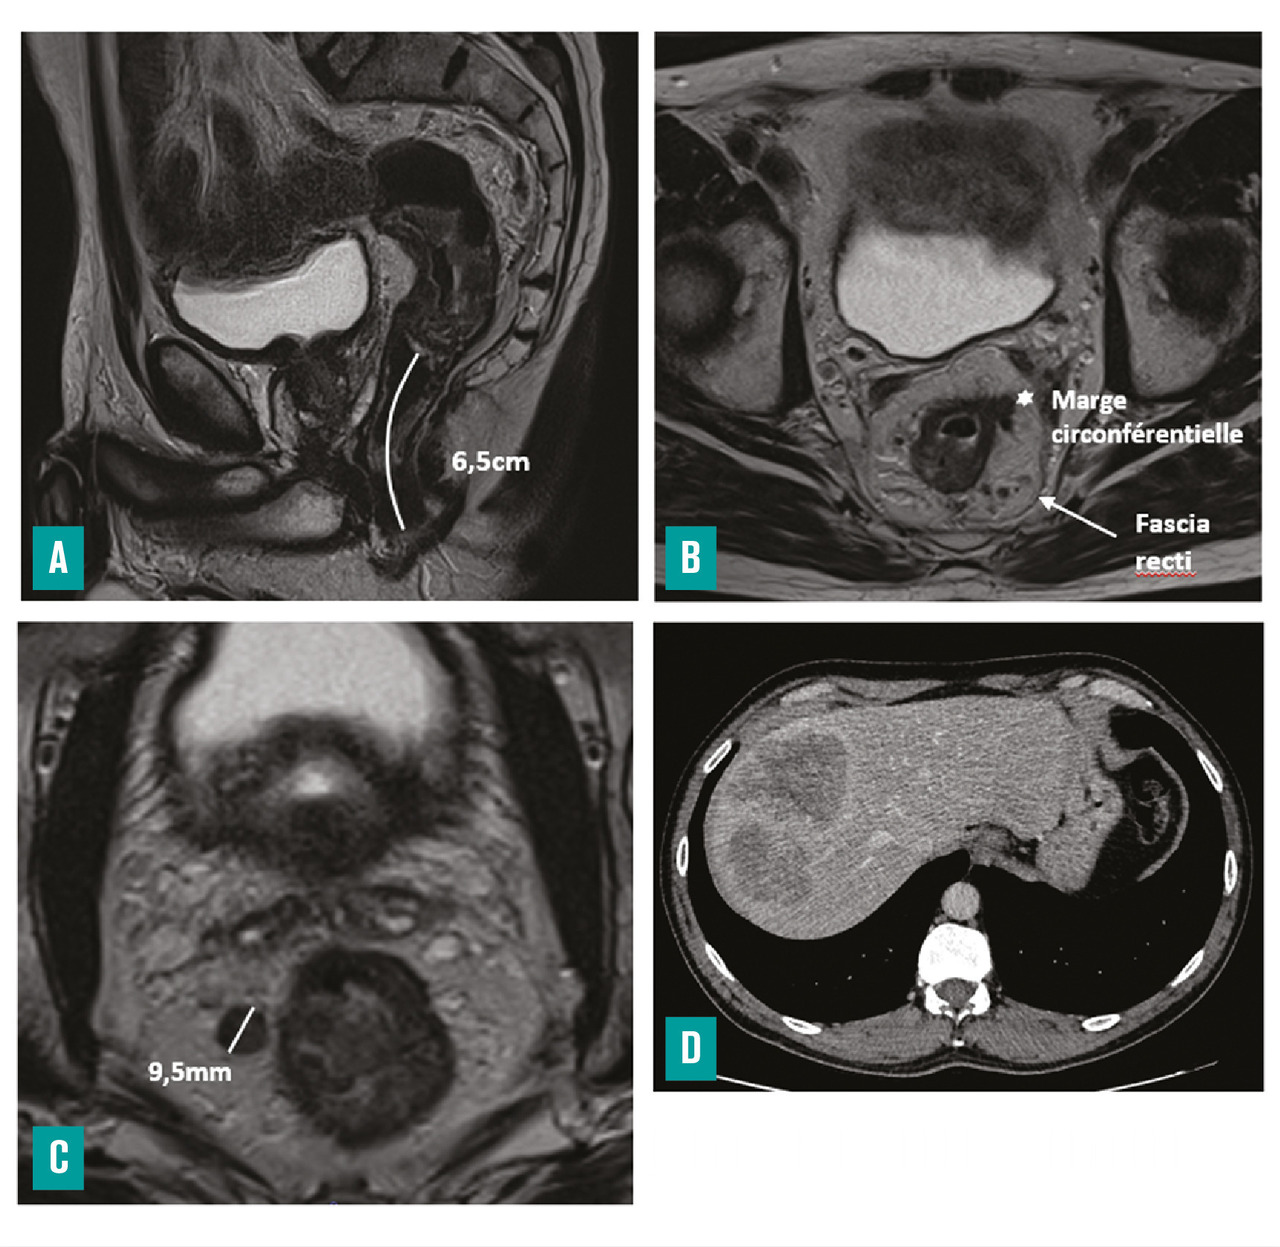

Le scanner thoraco-abdomino-pelvien évalue l’extension à distance

Le scanner thoraco-abdomino-pelvien permet de réaliser le bilan d’extension à distance du cancer du rectum, à la recherche, en particulier, de métastases hépatiques et pulmonaires.

Il doit comporter une injection de produit de contraste iodé. En cas de contre-indication à cette injection (insuffisance rénale évoluée, par exemple), réaliser une IRM hépatique et un scanner thoracique sans injection est une alternative.9

Le scanner est nettement moins performant que l’IRM pour le bilan d’extension locale du cancer du rectum, en particulier pour les tumeurs peu avancées.10